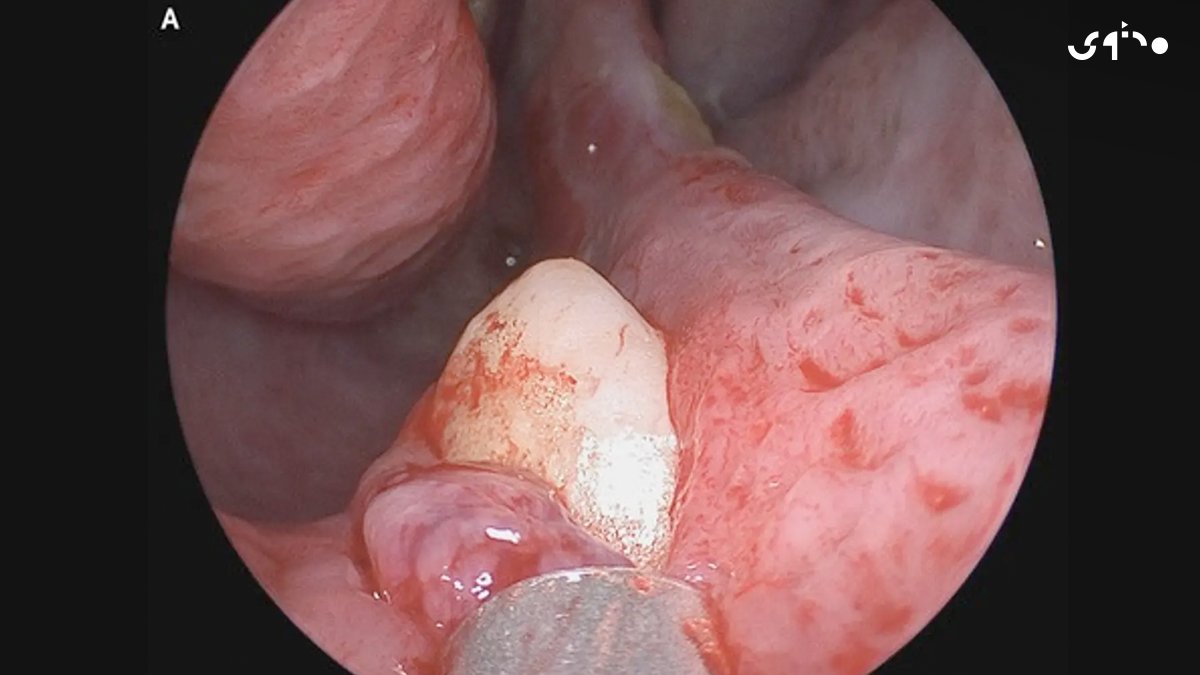

عانى شاب يبلغ من العمر 38 عاماً في نيويورك من انسداد بالمجرى التنفسي ليكشف التصوير المقطعي عن سن مقلوب في تجويف الأنف الأيمن يبلغ طوله 14 مليمتراً وعرضه 10 مليمترات وعلى الفور تمت إزالة السن جراحياً في مستشفى "ماونت سيناي"

سجلت حالة أخرى لرجل ستيني أخبره أطباؤه على مدى عامين أنه يعاني من تراكم للأوساخ في فتحة أنفه اليسرى نتيجة لعدوى بكتيرية ما جعله في نهاية المطاف يفقد قدرة الشم تماماً في الشق المصاب ليخضع بعد ذلك لفحوصات أكثر دقة كشفت عن نمو سن داخل أنفه وتم استئصاله على الفور وإصلاح أنسجة الأنف